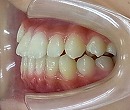

治療前 治療後

治療後の写真では、咬合バランスが改善しています。

今後、永久歯の矯正によって、美しい歯並びに改善していく予定です。